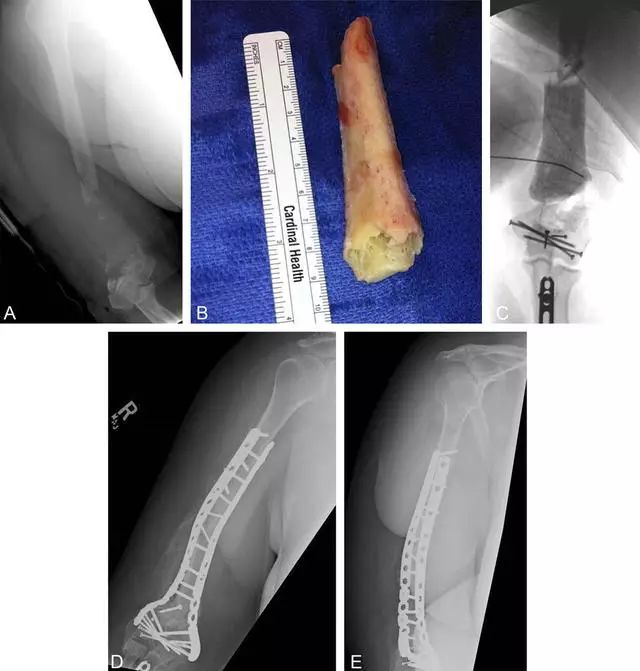

病例三

胫骨远端开放性骨折,远端骨折块游离在体外

游离骨块浸泡在抗生药物生理盐水溶液中

X 线片可见骨块寄养在自体下腹部皮下

创口清创、大量冲洗以后一期外固定支架固定,缺损区域抗生素骨水泥填充

二期回植,更换为钢板内固定

回植后 8 个月,骨折无感染迹象

另一例 48 岁男性,大块的胫骨骨折块,12 周以后从腹部皮下取出骨折块,图 B,去除再血管化的软组织

38 岁女性,肱骨长段骨缺损,10 cm 长骨块游离污染,一期抗生素骨水泥填充。回植后 10 个月骨折顺利愈合